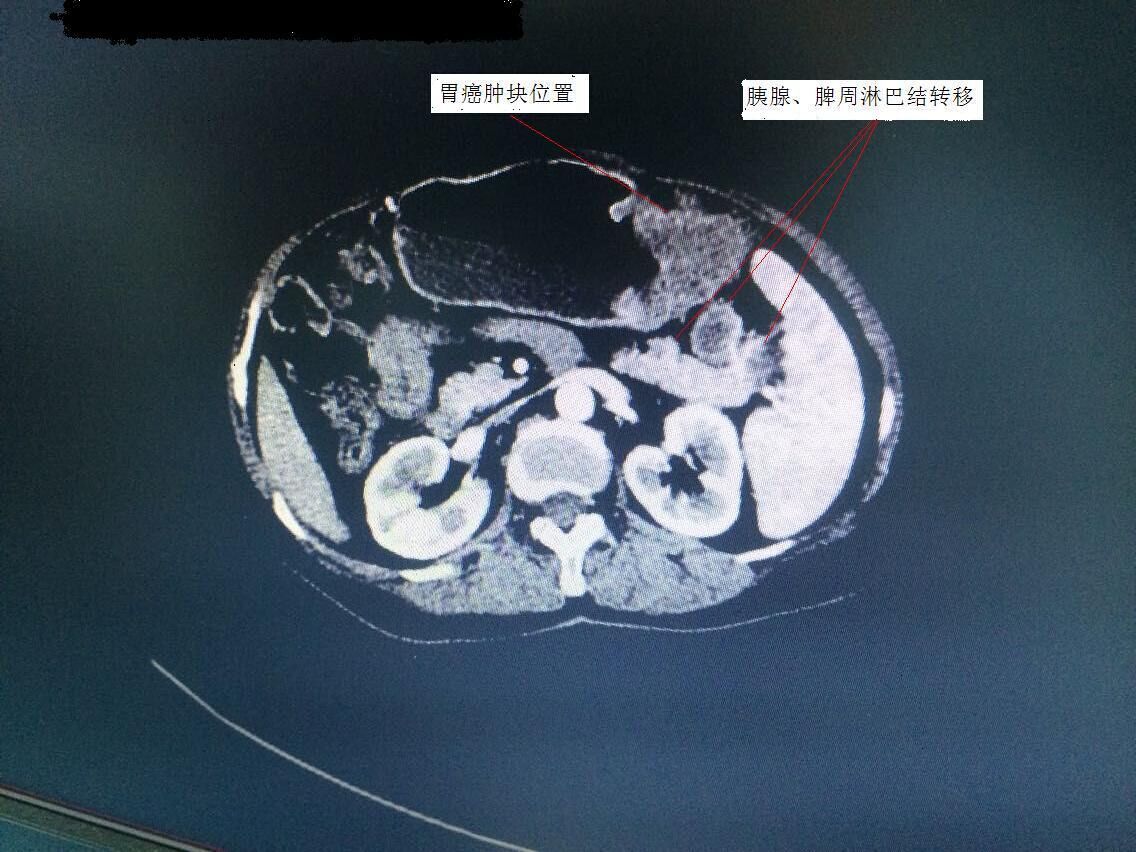

胃腸外科譚曙光主任率領(lǐng)科室團(tuán)隊(duì),術(shù)前對(duì)手術(shù)方案進(jìn)行了仔細(xì)研究。該患者胃癌腫塊位于胃體,腫塊較大,且胰腺尾部、脾門等周圍淋巴結(jié)轉(zhuǎn)移(見圖1)。為保證治療效果,提高患者生存質(zhì)量,需行全胃、胰腺體尾部以及脾臟聯(lián)合切除。此等手術(shù)在以往傳統(tǒng)開腹方面均具有較高難度,若想在微創(chuàng)下完成切除,更是難上加難。經(jīng)過科室嚴(yán)密的探討,最終確定為該患者行腹腔鏡下微創(chuàng)手術(shù)。手術(shù)歷時(shí)3個(gè)小時(shí),在手術(shù)室及麻醉科的配合下,順利完成衡陽市第一例腹腔鏡下胃癌根治聯(lián)合脾臟、胰腺體尾部切除術(shù)(術(shù)后標(biāo)本見圖2)。術(shù)后,該患者恢復(fù)良好,手術(shù)疤痕不到傳統(tǒng)手術(shù)的四分之一(見圖3),目前已開始術(shù)后化療。

圖1